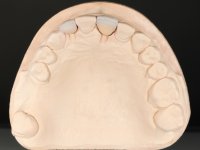

Treatment began with re-preparation of the cast post and core, with the purpose of placing the cervical finishing lines with an intra-sulcular location and simultaneously making a suitable temporary crown. With a very simple orthodontic treatment, the diastema was closed between the upper central incisors, and this position was stabilized with a wire placed on the palatal surface of the central, functioning as containment. Later, a slow orthodontic traction of tooth 2.2 was attempted, in order to reduce, although very slightly, the vertical bone loss in this area. At the end of the traction, tooth 2.2 was extracted and the area was provisionally rehabilitated with a composite resin crown bonded to the adjacent teeth. A dental implant was placed in the area of tooth 2.2 and the temporary crown was again bonded to resin, provisionally rehabilitating the patient during osseointegration. In tooth 1.3 a gingivectomy with an electric scalpel was performed, with the intention of raising the cervical level of 1.3 achieving greater harmony with tooth 2.3. Stabilized soft tissues were impressed using the open tray technique with putty and light addition silicones. Collection of the color of both the dental component and soft tissues was done by the ceramist in the office. In the laboratory, the impressions were transferred to plaster and gave origin to work models that were properly analyzed. It was decided to assemble a metal-ceramic abutment screwed onto the implant. This abutment was cast with a noble alloy and subsequently coated with coronary and gingival ceramics. Due to the inclination of the implant, the screwing inevitably conditioned the exit of the screw hole through the vestibular surface. In order to conceal this situation, the design of the abutment has already been conceived with the intention of accommodating on the vestibular surface the bonding of a feldspathic veneer. This abutment was tested in the mouth and adjustments were made in the gingival ceramic component. Its adaptation to the soft tissues was done in a subtractive way, with a drill, as well as additive, adding resin composed of gingival tonality.

This addition of resin would guide the ceramist in the final placement of the gingival tonality ceramic. The crown that would rehabilitate tooth 1.3 was cemented in this test session with glass ionomer cement, reinforced with composite resin. Once the laboratory work was finished on the veneer for tooth 1.2, the abutment, and the veneer for the implant, this was bonded in the mouth, after placement of the absolute insulation. The work completely satisfied the patient. For eight years, the patient had periodical check-ups, and was pleased with the treatment, but also began to show interest in an aesthetical intervention on the upper central incisors. Once the second phase of our intervention was decided, dental preparation of teeth 1.1 and 2.1 was performed for the placement of two feldspathic veneers. Particular care was taken in the distal inter-proximal preparation adjacent to the abutment of the implant.